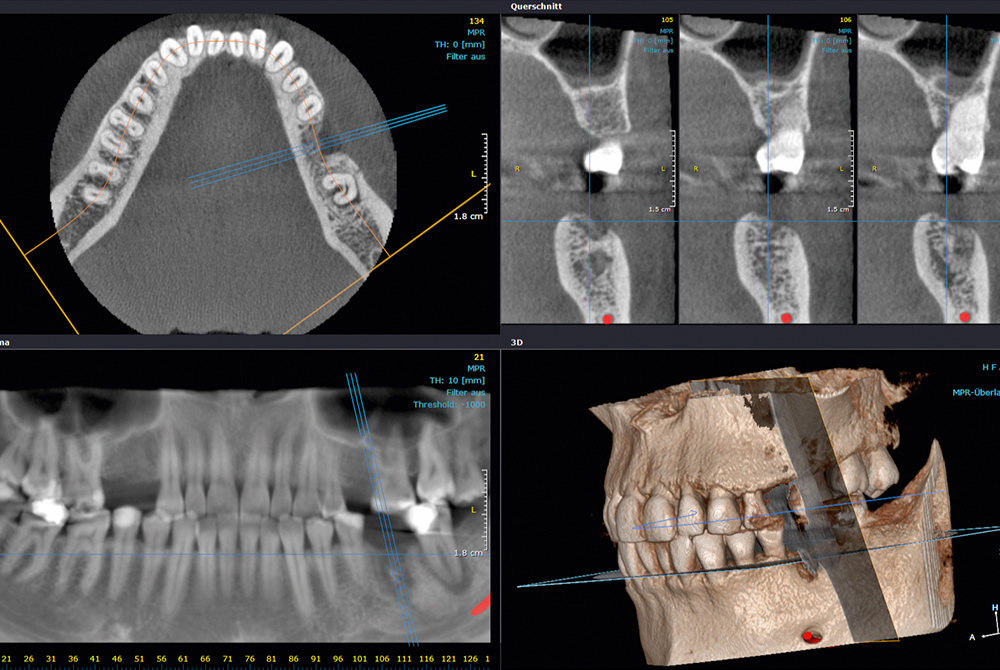

CBCT dijagnostika

Visok stupanj uspješnosti zahvata kod stomatologa baziran je na vrhunskim dijagnostičkim uređajima. Zahvaljujući kvalitetnoj dijagnostici, doktor dentalne medicine, na najbolji mogući način dobiva precizan uvid u stanje zuba i cijele usne šupljine kako bi postavio točan plan terapije...